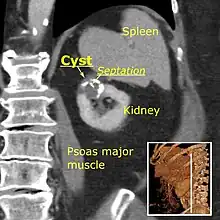

Category IIF

This category includes renal cysts with multiple thin septa, a septum thicker than hairline, slightly thick wall, or with calcification, which may be thick. It also includes intrarenal cysts larger than 3 centimetres (1.2 inches) if:

- there is no contrast enhancement (otherwise category III).[7]

- there is high attenuation or there is a maximum 25% of their walls visible outside the kidney (otherwise category II).[3]

Category IIF cysts have a 5–10% risk of being kidney cancer, and therefore follow-up is recommended. However, there is no consensus recommendation on the appropriate interval of follow up.[7]

Bosniak II cyst at the lower pole of right kidney with septations within.